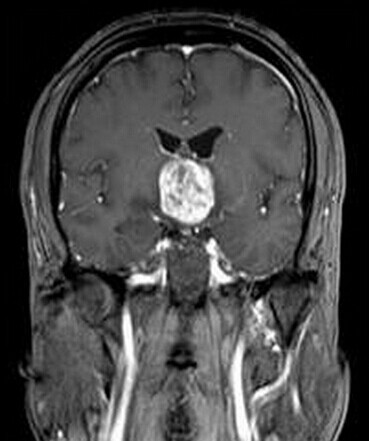

患者:男,50岁,记忆力下降1月余,双眼视力下降,反应减慢。

【正确答案】D 胶质瘤(第三脑室脊索样胶质瘤)

第三脑室脊索样胶质瘤的特征性表现是:

(1)见于成人,边界清楚,位于第三脑室前部;

(2)T1WI上为低信号,T2WI上呈明显高信号;

(3)增强后明显强化;

(4)肿块累及视交叉及下丘脑,但不浸润周围脑实质。